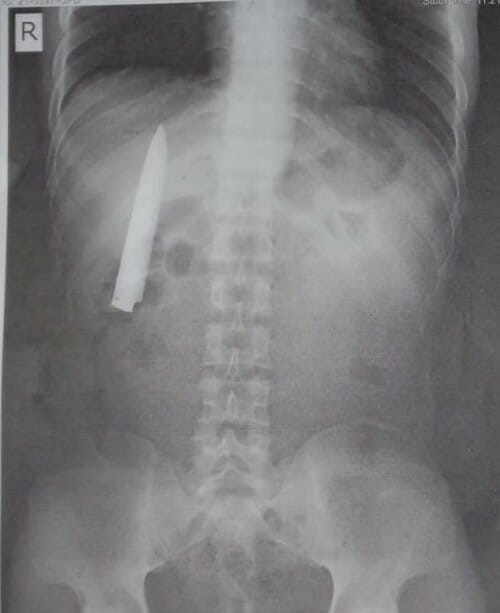

ហ្វីលីពីន៖ បុរសម្នាក់បានទៅពិនិត្យសុខភាពដើម្បីបំពេញតាមលក្ខខណ្ឌរបស់ក្រុមហ៊ុនដែលបានគាត់បានដាក់ពាក្យចូលធ្វើការងារ ស្រាប់តែទទួលបានលទ្ធផលគួរឲ្យភ្ញាក់ផ្អើលបំផុតមួយដោយការថត X-Ray បានបង្ហាញថា នៅក្នុងឆ្អឹងទ្រូងរបស់គាត់មានជាប់កូនកាំបិតមួយជាងមួយឆ្នាំមកហើយ។

បើយោងតាមការចុះផ្សាយនៅក្នុងសារព័ត៌មាន World of Buzz បានឲ្យដឹងថា បុរសរូបនេះមានឈ្មោះ Kent Ryan Tomao ជាជនជាតិហ្វីលីពីន និងមានអាយុ ២៥ ឆ្នាំ ហើយកាលពីថ្ងៃទី ៤ ខែ មករា ឆ្នាំ ២០២០ កន្លងទៅនេះ រូបគាត់ត្រូវបានក្រុមក្មេងស្ទាវចាក់ជាច្រើនកាំបិតចំទ្រូងនិងត្រូវបញ្ជូនទៅសម្រាកព្យាបាលនៅក្នុងមន្ទីរពេទ្យរដ្ឋមួយកន្លែង ខណៈដែលពេលនោះគាត់មានរបួសយ៉ាងធ្ងន់ធ្ងរស្ទើរតែស្លាប់បាត់បង់ជីវិតទៅហើយ។

បន្ទាប់ពីសម្រាកព្យាបាលរបួសនៅក្នុងមន្ទីរពេទ្យមួយរយៈមក លោក Kent Ryan Tomao ក៏បានត្រលប់ទៅផ្ទះជាធម្មតាវិញ ហើយចាប់តាំងពីពេលនោះមកសុខភាពរបស់គាត់ក៏បានវិលទៅរកភាពធម្មតាវិញដែរ ពោលគឺគ្មានការឈឺចាប់ណាមួយកើតឡើងឲ្យគួរគត់សម្គាល់នៅលើទ្រូងរបស់គាត់នោះទេ។ ថ្មីៗនេះលោក Kent Ryan Tomao បានដាក់ពាក្យចូលបម្រើការងារនៅក្នុងក្រុមហ៊ុនឯកជនមួយកន្លែង ដែលក្រុមហ៊ុននោះតម្រូវឲ្យគាត់ត្រូវទៅពិនិត្យសុខភាពនិងថត X-Ray ពិនិត្យសួតជាចាំបាច់ ហើយគាត់ក៏ទទួលបានលទ្ធិផលដ៏សែនហួសចិត្តនេះតែម្តង។

លោក Kent Ryan Tomao បានឲ្យដឹងថា គាត់នឹងត្រលប់ទៅកាន់មន្ទីរពេទ្យដែលបានព្យាបាលរបួសឲ្យគាត់ឡើងវិញដើម្បីឲ្យគេវះកាត់យកកូនកាំបិតនេះចេញ តែគាត់គ្មានគម្រោងប្តឹងមន្ទីរពេទ្យនោះទេ បើទោះជាខាងមន្ទីរពេទ្យមានភាពខ្ជីខ្ជារហូតបានបន្សល់ទុកកូនកាំបិតមួយនៅក្នុងខ្លួនរបស់គាត់ជាងមួយឆ្នាំមកនេះក៏ដោយ៕